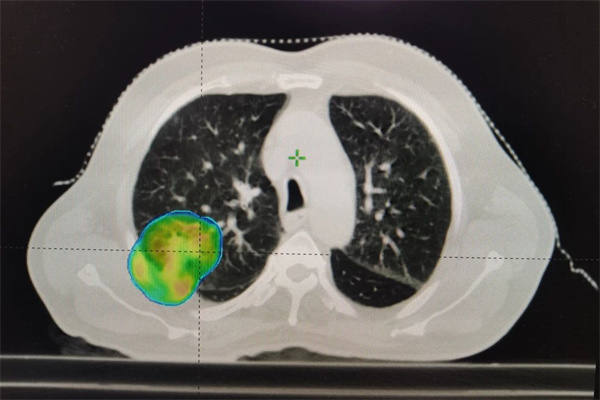

2017年右肺上叶肿物精准放疗计划

为确保最佳治疗效果,同时降低副反应,我们放疗团队仔细查阅了韩大爷7年前的放疗方案(针对右肺上叶)。经过全面的评估和讨论,我们决定为他量身定制新的放疗计划,针对现阶段右肺下叶的肿物进行精准放疗。在新的治疗方案中,我们对放疗计划不断优化进行剂量雕刻,以最大限度地减少对周围肺健康组织的损伤,并确保治疗的精确性和安全性。新的放疗计划一经制定,便立即启动了治疗程序。